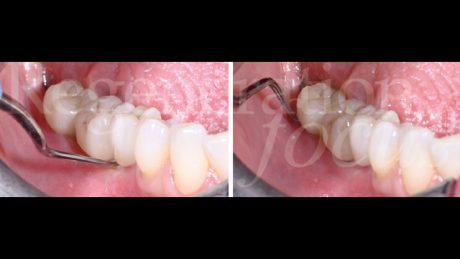

Il periodo di osteointegrazione è trascorso senza complicanze (Fig. 13). A quattro mesi, l’impronta digitale con scanner intraorale ha registrato la morfologia dei tessuti molli maturati (Fig. 14). Le corone monolitiche in zirconia stratificata sono state progettate e realizzate (Odt. Antonio Corradini) con emergenza graduale per supportare i tessuti molli, sfruttando la connessione diretta delle corone protesiche senza l’utilizzo di monconi o cemento, eliminando micro-gap e micro-movimenti in grado di compromettere la stabilità del sigillo biologico (Fig. 15).

Il follow-up clinico e radiografico a 12 mesi ha documentato eccellente stabilità del risultato ottenuto. L’analisi radiografica non ha evidenziato rimodellamento osseo marginale né segni di radiolucenza peri-implantare o alterazioni della trabecolatura ossea (Fig. 16). I parametri clinici peri-implantari hanno mostrato profondità di sondaggio inferiori a 4 mm e assenza completa di sanguinamento al sondaggio. L’analisi del fenotipo tissutale ha documentato incremento significativo dello spessore mucoso e l’analisi del microbioma ha rivelato composizione batterica compatibile con la salute peri-implantare e il mantenimento dell’eubiosi (Figg. 17,18).